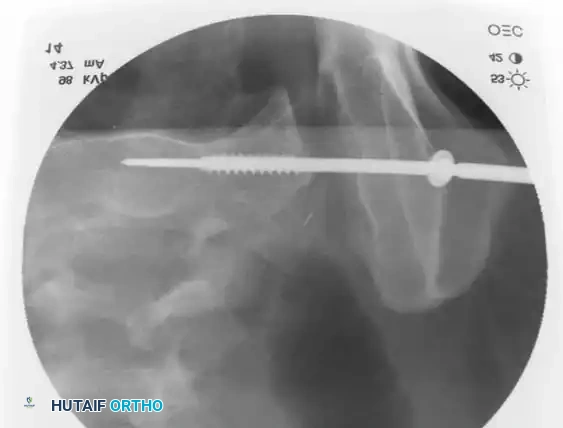

3. Percutaneous Sacroiliac (SI) Screws (Posterior Ring)

The gold standard for posterior ring fixation in appropriately selected patients.

* Indications: Sacral fractures, SI joint disruptions, crescent fractures.

* Technique: Performed under strict fluoroscopic guidance (Inlet, Outlet, and Lateral sacral views).

* Trajectory: The guide wire is advanced from the lateral ilium, across the SI joint, into the S1 (or S2) vertebral body.

* Safety Corridors: The surgeon must possess an intimate understanding of sacral dysmorphism. The "safe zone" is bounded by the sacral neural foramina inferiorly, the spinal canal posteriorly, and the sacral ala anteriorly.

Pitfall: Failure to recognize a dysmorphic sacrum (characterized by upper sacral segment elevation, non-recessed alae, and oblique neural foramina) can lead to catastrophic L5 nerve root injury or vascular penetration during SI screw placement.

Intraoperative Fluoroscopy and Reduction Techniques

Image